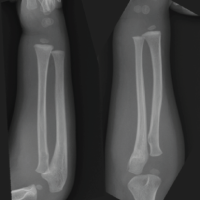

A below-knee cast immobilization was completed for 2 months. Consolidation is obtained in 2 months, allowing full weight bearing. The patient was regularly followed up. At 2-month follow-up, ankle mobility was normal, comparable to the left ankle, with dorsal flexion at 25° and plantar flexion at 45°, and the follow-up X-ray at 2 years showed no signs of recurrence (Fig. 6). Five years later, the patient had no complaints.